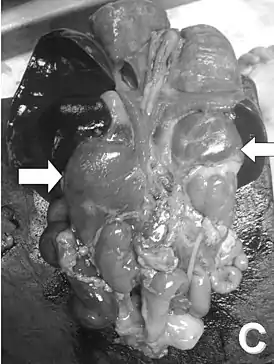

![]() Вскрытие новорождённого. Стрелками указаны увеличенные надпочечники | |